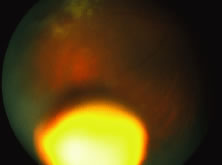

A disseminated form of congenital HSV occurs with involvement of the brain and viscera, principally the liver, adrenal glands, kidneys, lungs, and gastrointestinal tract. The child typically presents with fever, poor feeding, hypoactivity, and respiratory difficulty (Fig. 30). This is the most severe form of congenital herpetic disease with the poorest prognosis. More localized forms of congenital HSV infection may include the CNS, eyes, skin, or oral cavity. Overall, 20% of neonates contracting herpetic infections have ocular involvement.125

Fig. 30. Herpes simplex retinitis in a newborn manifested by fulminant panretinal involvement of white areas of retinitis and variable hemorrhage. The child also suffered from herpetic encephalitis and skin disease.

Herpetic retinitis in neonates has a characteristic appearance. Cogan and colleagues78 first described this in 1964. Generally, the lesions consist of large patches of yellow to white retinitis in an equatorial distribution, although more anterior or posterior lesions may be observed. Coalescence of the lesions may occur resulting in massive involvement of the retina (see Fig. 27). A marked vitreitis and retinal vasculitis may be seen. If a diagnosis of neonatal HSV retinitis is made, intravenous treatment with acyclovir is recommended.